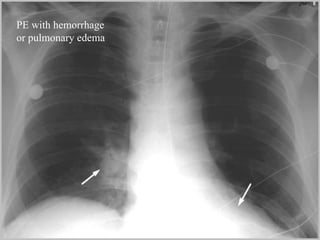

PE with hemorrhage or pulmonary edema

PE with hemorrhageor pulmonary edema